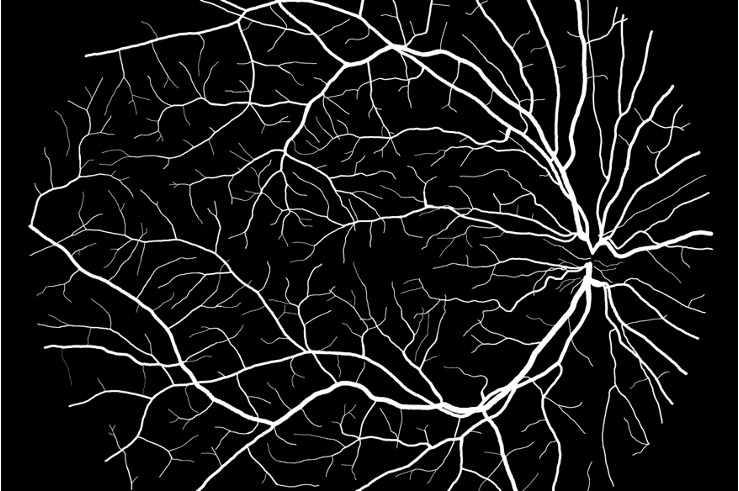

Figure 3: Qualitative results on all three segmentation tasks. The figure shows an example image, ground truth (GT) and predicted (PRED) segmentation mask for the skin lesion segmentation task (row 1), the polyp segmentation task (row 2) and retinal vessel segmentation task (row 3).

We have provided the additional qualitative results of our method for all three segmentation tasks. Fig. 5, shows the qualitative results of skin lesion segmentation, while Fig. 6 and Fig. 7, illustrate the visualization of retinal vessel and polyp segmentation tasks respectively.

Refer to caption

IMAGE

GROUND TRUTH

PREDICTED MASK

Figure 6: Visualizations of retinal vessel segmentation